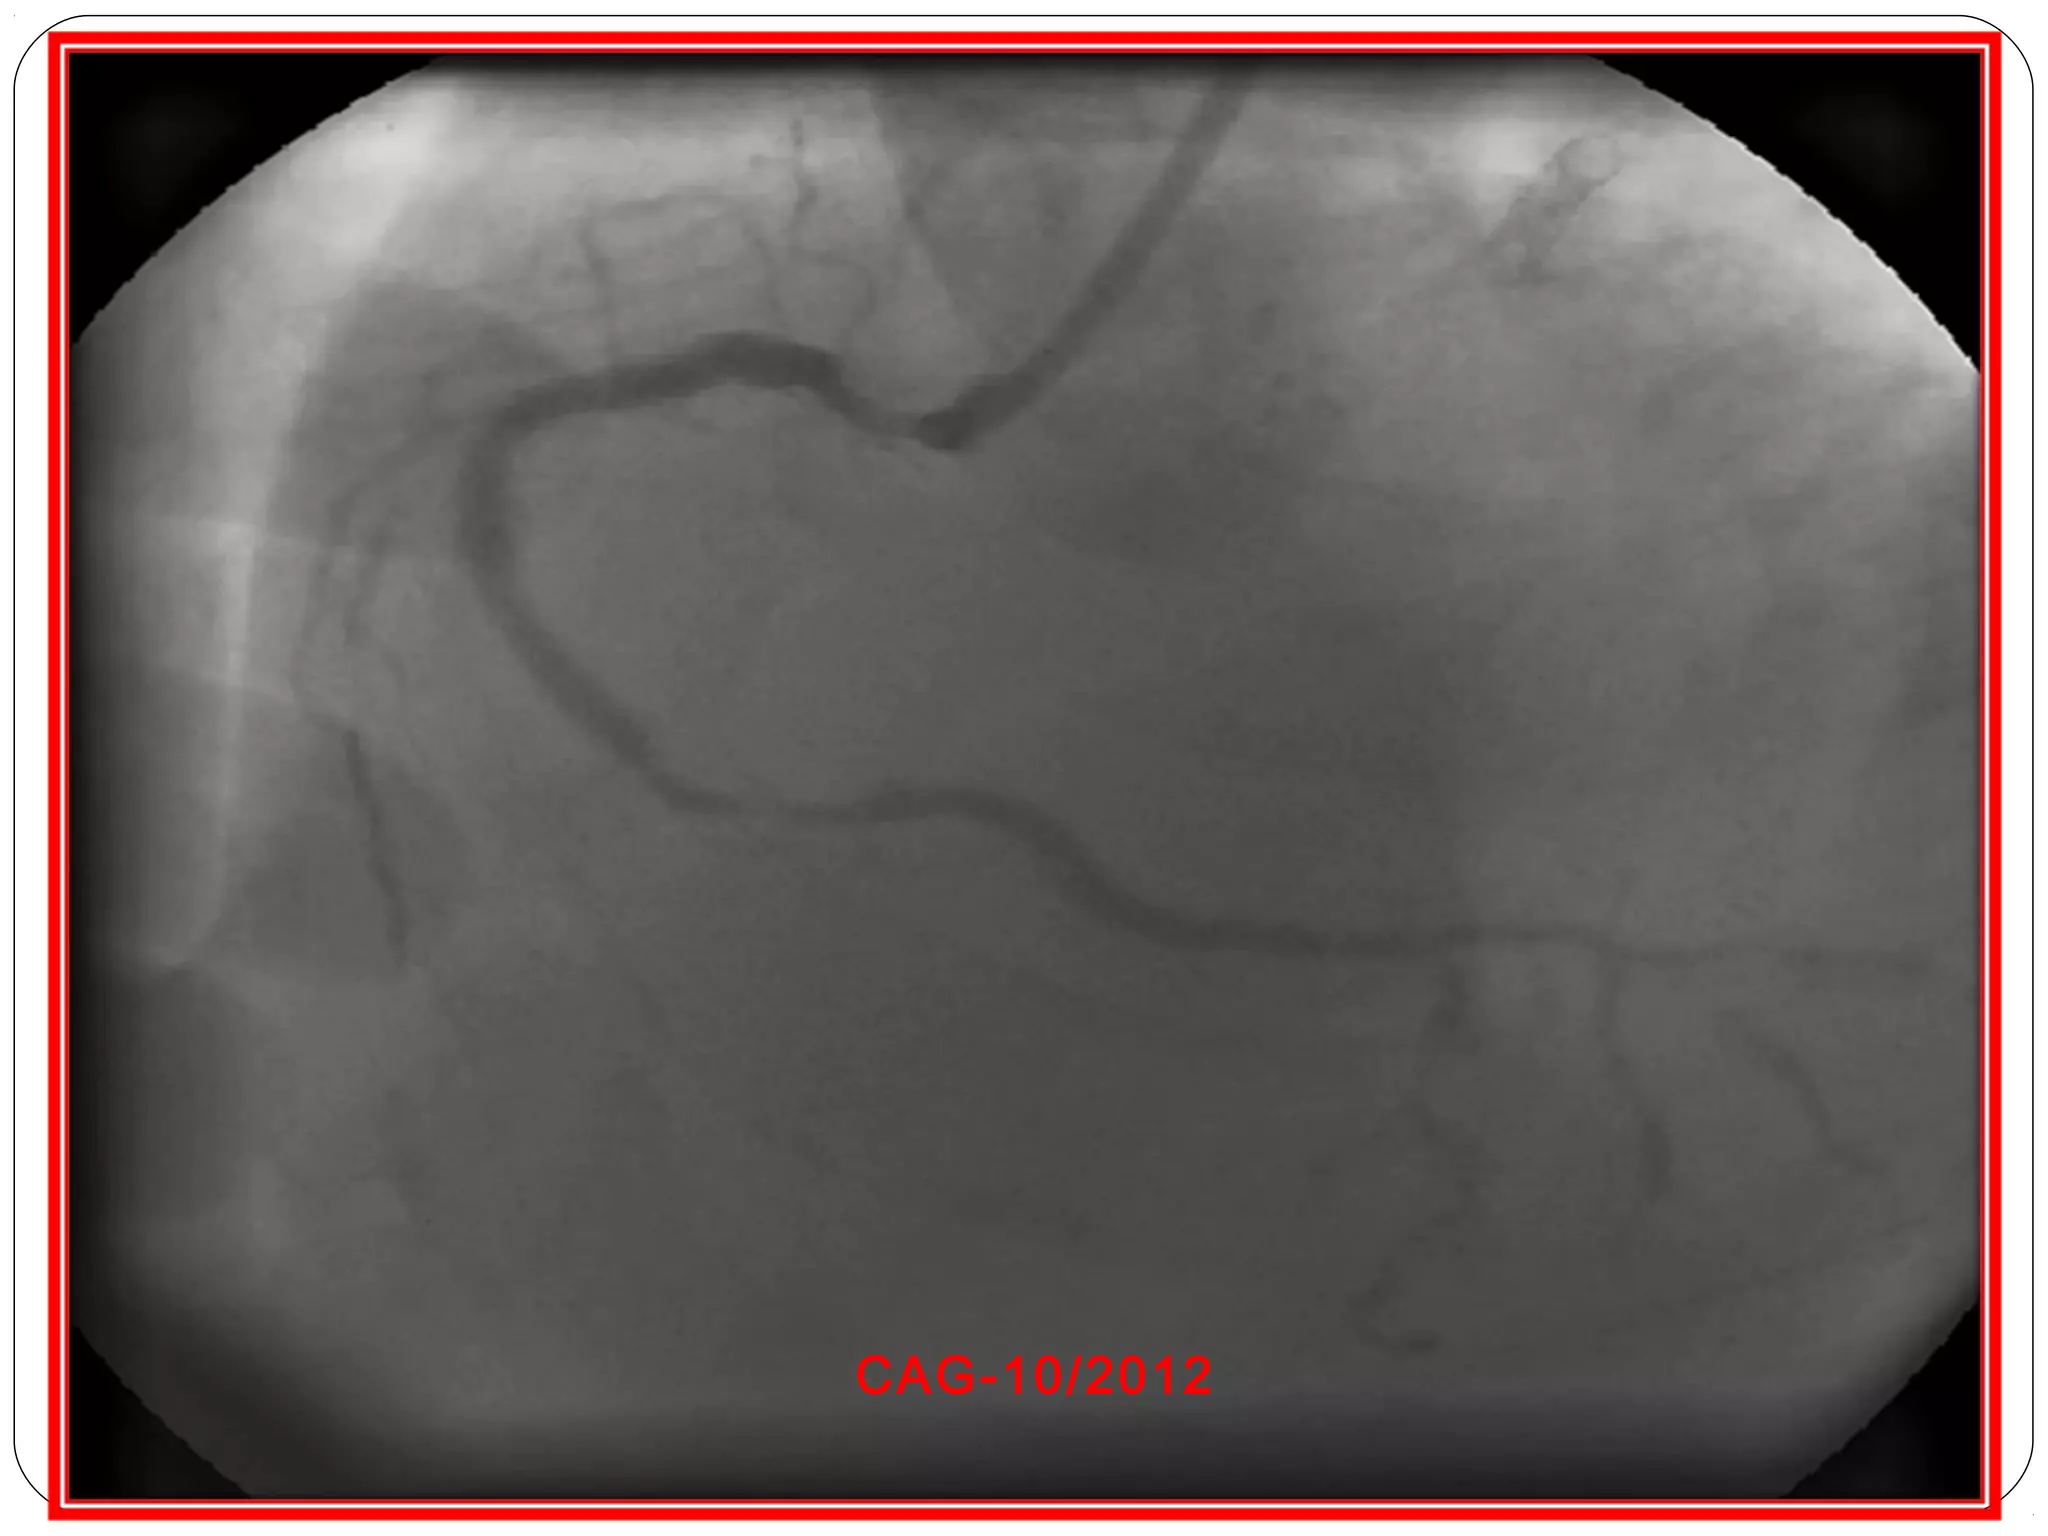

• Cardiac Catheterization: This invasive procedure involves inserting a catheter into the heart to measure pressure and blood flow, and to visualize the coronary arteries.